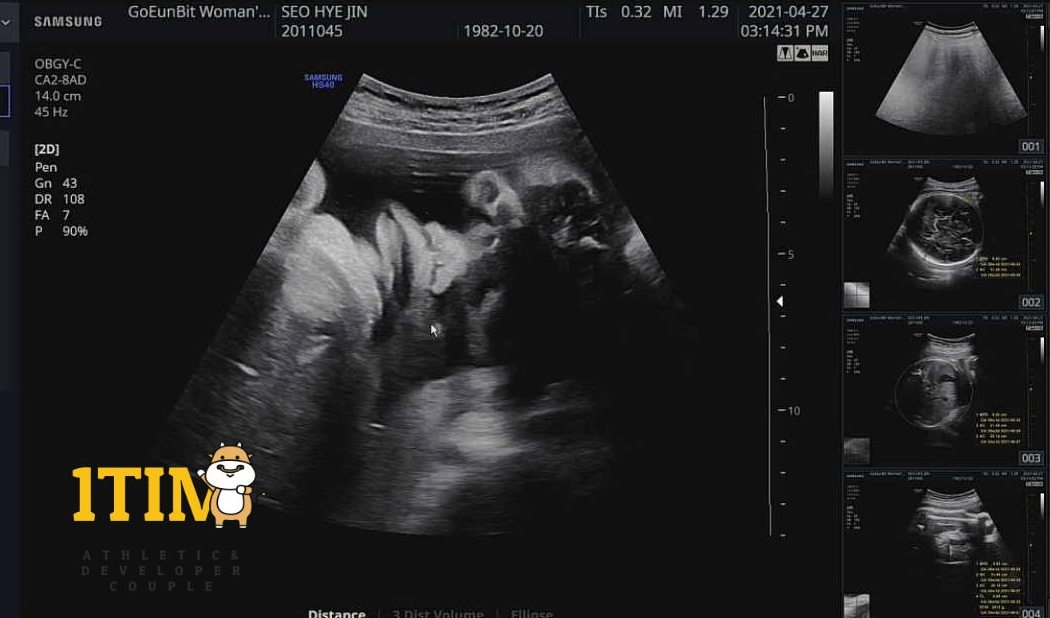

촘파 사진 그동안 참 귀여웠는데..

크롱아 너 왜 고릴라 같이 생겼어...?

웨 때문에 그렇게 넙대대 한거야??? 하하하 눙물 ㅠㅠ

아니지? 눌려서 그런거지?? 껄껄